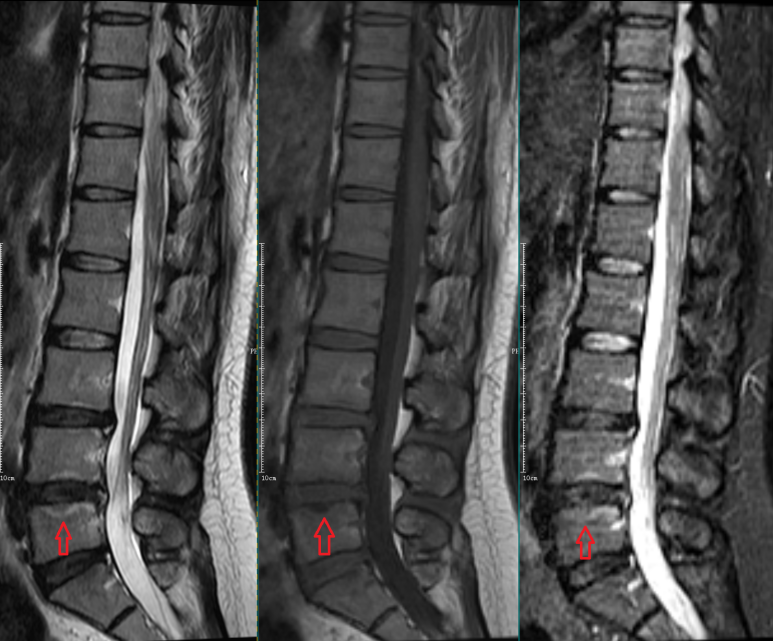

患者术前mir检查:腰5骶1椎间盘脱出伴终板炎